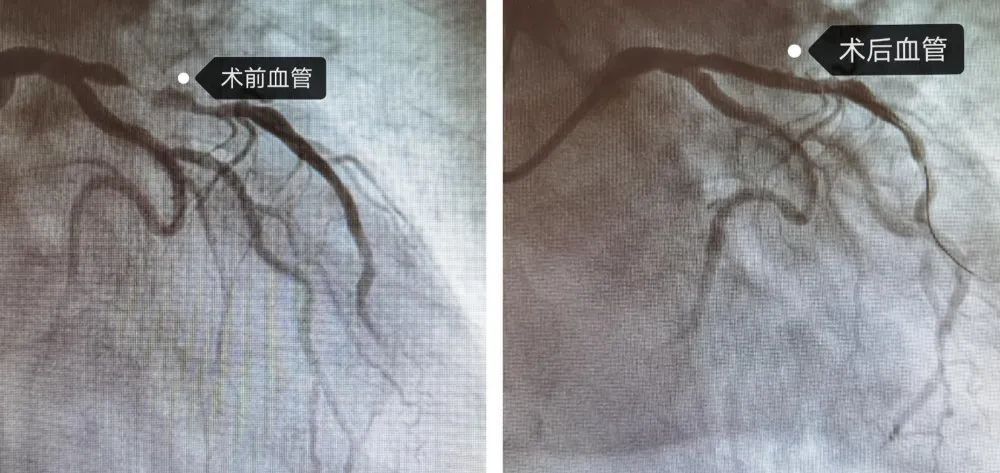

5月27日,张新勇如约而至,与心内二科专家一起为袁老先生进行了冠状动脉介入治疗。术中冠状动脉造影检查显示,袁老先生左侧冠脉血管前降支近段可见弥漫性狭窄,最严重的可达99%,经过认真评估后,顺利为其行冠脉支架植入术。术后,袁老先生胸闷、胸痛及活动后气短等不适症状消失,老人和家属对治疗效果十分满意。